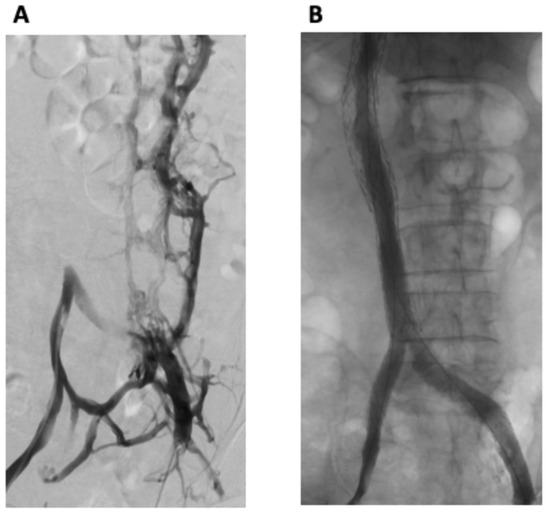

2. Detailed Case Description